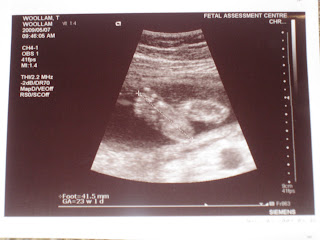

Talking about the little Baby Woollam, we had another visit to our doctor this afternoon, unfortunately we don't get any more photos to take home with us, due to the little baba getting to big to photograph, but it was still so great to see the little heartbeat and see how beautifully big s/he has gotten. At an estimated weight of +/- 780g, almost 200g bigger than our last scan 2 weeks ago. We couldn't get a full size, 'cause our little munchkin decided to curl his/her little legs and totally bend it's little neck, which made it totally impossible for Dr Graves to do a proper measurement. My tummy is getting bigger and bigger by the day and we can now even see the little kicks, bumps and punches by just watching the bump. Such an active little baba!